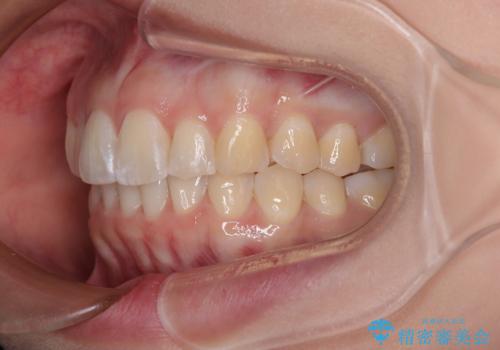

- 前方に主張した前歯2本を気にして来院された患者様です。

下顎前歯がデコボコしており、その影響で上顎前歯が前方に押し出されている状態でした。

口元が閉じにくいという印象はなかったため、非抜歯矯正にて歯列を整えていくこととしました。

上下左右の親知らずを抜歯し、上下ともに歯列を後方と側方に拡大し、口元を突出させることなくデコボコを解消することとしました。

前歯の形が台形であり、歯列が整ったところでブラックトライアングルが目立つ仕上がりとなったため、IPR(歯と歯の間を削る処置)によって歯の形態を修正し、隙間の目立たない歯列に仕上げることができました。